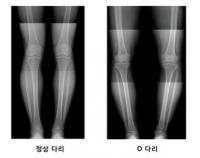

¹«¸ ÅëÁõ ȯÀÚ 2¸í Áß 1¸í O´Ù¸®

[¿Óóµ¥Àϸ®] XÀÚ·Î ºñ¶Ô¾îÁö°í,OÀÚ·Î ÈØ ´Ù¸®´Â º¸±â¿¡µµ ¾È ÁÁ...